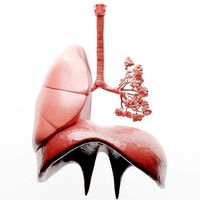

Diaphragm Muscle Group

...the diaphragm is a dome-shaped muscular partition separating the thorax from the abdomen in mammals. it plays a major...

Human Diaphragm

...the medical term a dome-shaped muscular partition separating the thorax from the abdomen in mammals. it plays a major...

Human Respiratory System Sculpt

...respiratory system lungs bronchi trachea larynx lobe osphagus epiglottis thorax sculpt...

Respiratory System

...realistic respiratory system lungs bronchi trachea larynx osphagus epiglottis thorax bronchial...

Human Respiratory System Lungs

...respiratory system lungs bronchi trachea larynx lobe osphagus epiglottis thorax ...